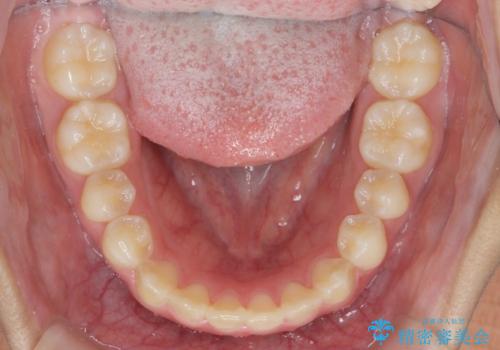

インビザラインで行う八重歯の治療

- 笑った時に目立つ八重歯の矯正治療を求めて来院されました。

マイクロインプラントを用いた臼歯の後方牽引、およびゴムかけ等の付加処置を駆使して八重歯の治療を行っていきます。

しっかりとゴムかけを頑張っていただいたおかげで、上顎臼歯の後方移動が達成されしっかりとした噛み合わせの構築と、八重歯の治療を達成することができました。